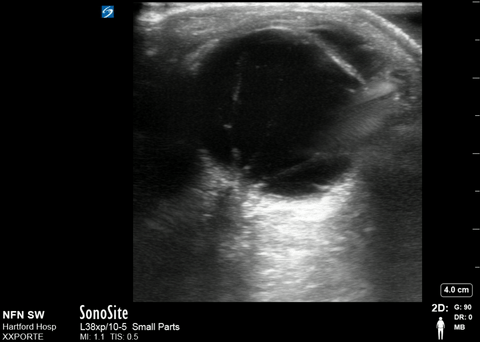

Both retinal detachment and vitreous hemorrhage

Courtesy of Shirly Wu, MD - UCONN EM Residency